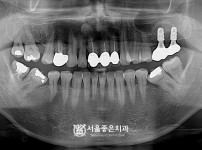

|  | 348 |  | 뼈이식 임플란트 4개 - 오스템 임플란트 / 오래전에 하신 브릿지 잇몸뼈 소실, 치아동요 심하여 발치 후 임…